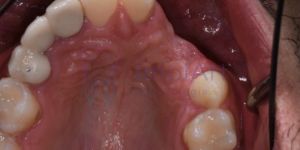

A técnica de prótese adesiva pode ser indicada inicialmente para restabelecimento estético, já que a ausência de um dente certamente impacta no visual do sorriso, principalmente nos dentes anteriores. Entretanto, a indicação da técnica adesiva é limitada para suprir algum dente na região posterior, principalmente por ser a área que mais recebe carga mastigatória. Provavelmente a prótese adesiva teria um problema de fratura ou soltura frequente devido ao estresse mecânico durante a mastigação. Basicamente as indicações mais comuns da prótese adesiva são:

- Reposição de um dente perdido na região anterior (incisivo central ou lateral).

- Reposição de segundo dente pré-molar.

- Como prótese provisória para ser utilizada no momento em que o implante dentário cicatriza.